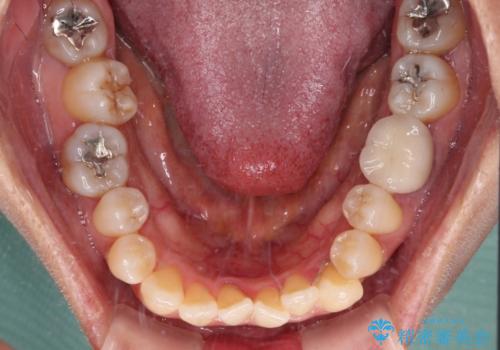

受け口と八重歯を改善 インビザライン矯正治療

- 前歯のデコボコや八重歯を治したいとのことで来院された患者様です。

受け口傾向の骨格であり、前歯はクロスバイトまたは切端咬合となっており、下顎を中心に歯列全体の後方移動を行い、IPR(歯と歯の間を削る)によってデコボコが解消するように設計し、インビザラインにより治療を行うこととしました。

受け口傾向のインビザライン矯正は比較的治療を行いやすいため、きれいに仕上げることができました。舌の突出癖が顕著であったため、改善のためのトレーニングをしっかりと行っていただきました。